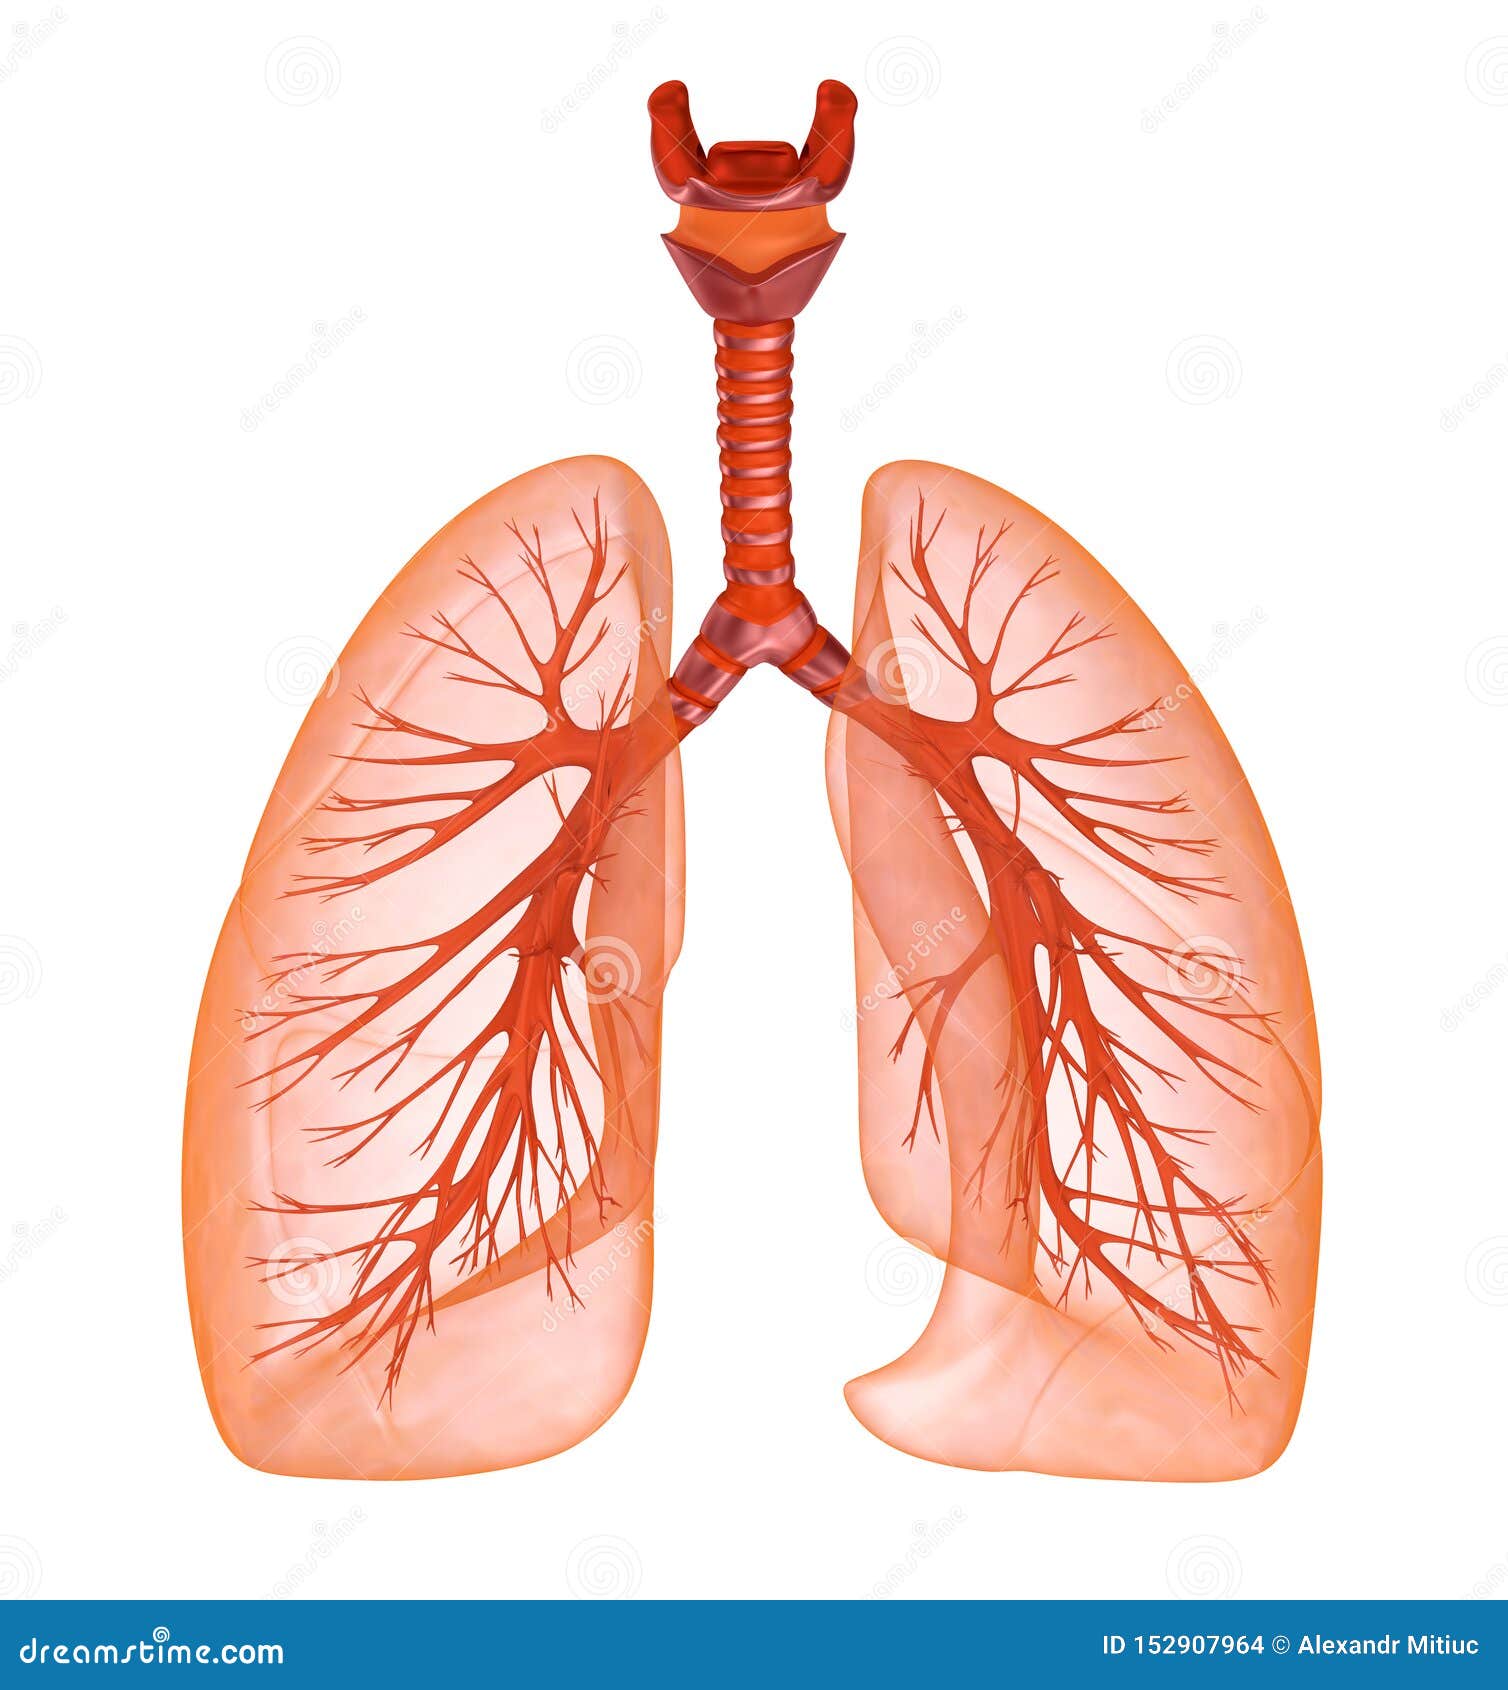

Обои для телефона с изображением лёгких человека